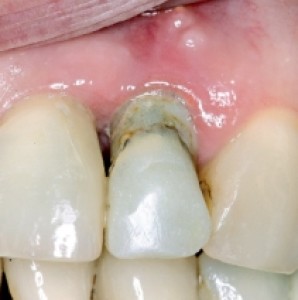

Obiettivi. Lo scopo di questo articolo è descrivere una serie di tecniche utili a migliorare l'estetica delle riabilitazioni implantari nel mascellare anteriore.Materiali e metodi. Si descrive...